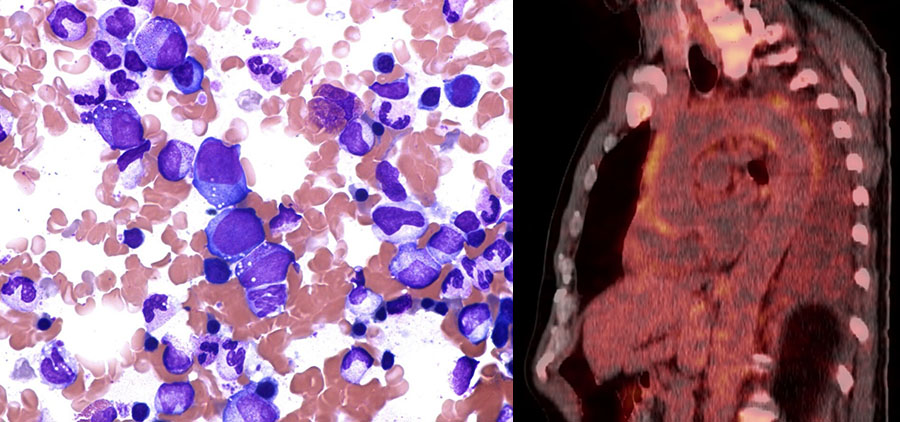

The patient's disease progressed despite ongoing treatment. He developed macrocytic anaemia with Hb 7–8 g/dL and MCV > 105 fL, and thrombocytopenia with platelets 20–30 × 109/L. A bone marrow smear revealed cytoplasmic vacuoles in erythroid and myeloid precursor cells (Figure 3), but repeated bone marrow smears and bone marrow biopsies were considered to be inconclusive as regards myelodysplasia or other bone marrow disease. Investigation with exome sequencing of DNA from blood and mucosa was carried out. The exome data were filtered using a targeted gene panel for hereditary anaemia or bone marrow failure and immunodeficiency diseases (7). The gene panel analysis included inspection of more than 300 genes, and no gene mutations were detected. Results of tests for amyloidosis and Whipple's disease were also negative.

Haematological manifestations are common in VEXAS syndrome (8). Cytoplasmic vacuoles in erythroid and myeloid precursor cells can be seen on bone marrow smear (Figure 3). Although these vacuoles are not specific to VEXAS syndrome, the syndrome should be suspected if cytoplasmic vacuoles are found in bone marrow cells. The disorder has many similarities with autoimmune manifestations seen in patients with myelodysplasia (9).